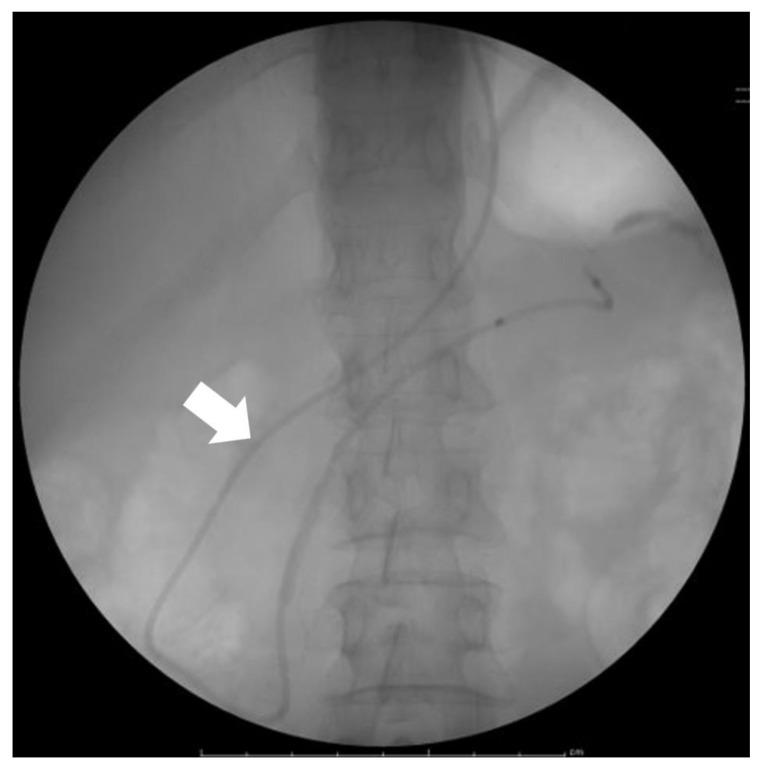

一种用于早期检测胰腺癌的新型诊断成像方法。

A Novel Diagnostic Imaging Method for the Early Detection of Pancreatic Cancer.

Diagnostics (Basel). 2023 Jun 15;13(12):2080. doi: 10.3390/diagnostics13122080.

DOI:10.3390/diagnostics13122080